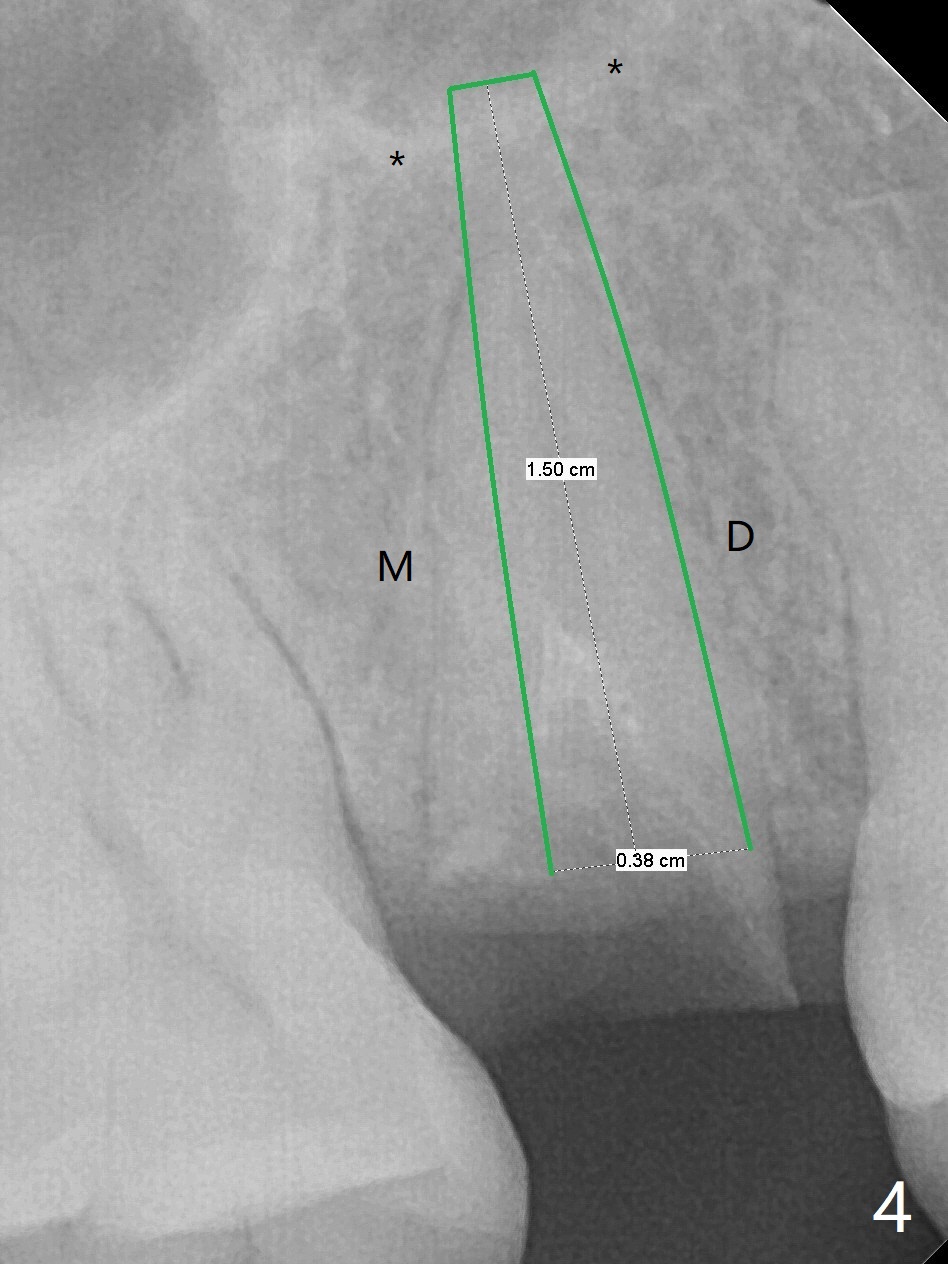

Barely Penetrate Sinus Floor

A 29-year-old woman requests implant for the residual root of the tooth #4 after initial RCT in home country (Fig.1,2 (S: sinus)). It appears that a 15 or 16 mm long implant should be placed to engage into the apical native bone and sinus floor (*) for stability (Fig.3,4). Further stability is obtained by contact with the mesial (M), distal (D) wall or both.